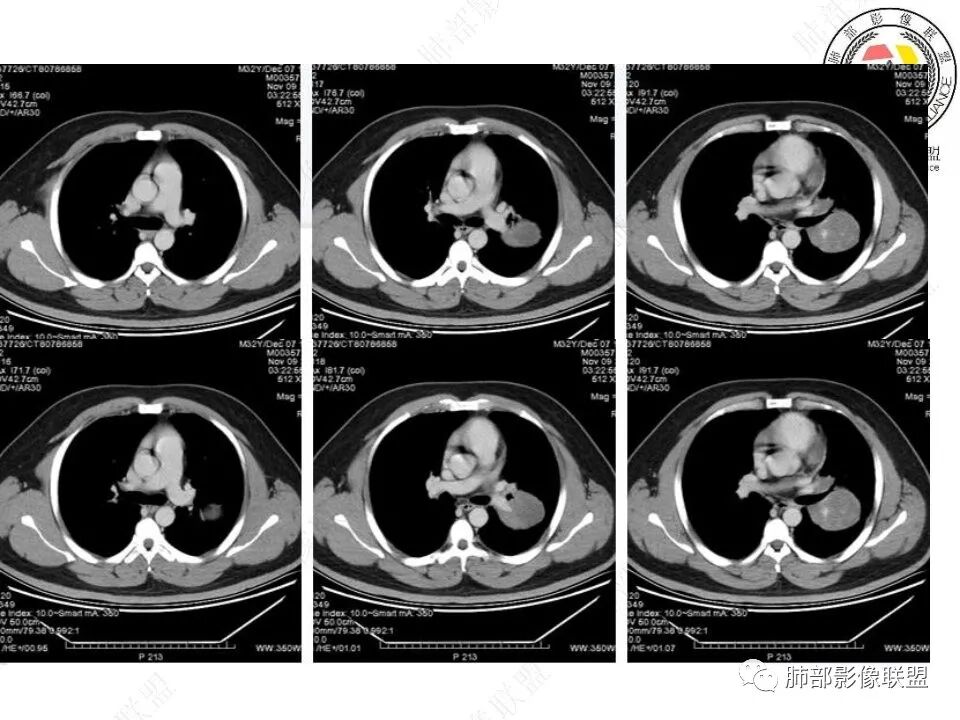

青年人,左肺下叶占位,边界清晰,支气管受包埋,病灶可见空气半月征,增强病灶内见血管影,纵膈未见增大淋巴结,考虑交界性肿瘤性病变,PSP,SFT,其次肉瘤类,鉴别淋巴瘤,小细胞癌。

左肺下叶巨大肿物,边缘光滑,支气管截断,蛇纹血管征?肿物远端可见空气新月征,恶性SFT ?肉瘤?

边缘圆盾,支气管截断,不均匀强化,新月征,恶,神经内分泌类,大细胞,鉴别间叶来源肉瘤。

青年男性患者,体检发现左肺下叶类圆形占位性病变,边界清楚,浅分叶,内部密度均匀,见血管,远端见不规则坏死,考虑恶性,肉瘤可能

青年男性,体检发现,左肺下叶肿块,边界清晰,支气管受压,病灶可见空气半月征,增强不均匀强化,内见血管穿行影,定位胸膜起源,PSP?SFT?肺内肉瘤类待排。

左肺下叶肺门区软组织密度肿块,支气管进入阻塞截断,边缘清晰,外后侧可见空气半月征。强化不均,内可见杂乱强化血管及低密度坏死,考虑恶性病变,肉瘤?鉴别CD。

青年男性,左下肺肿块,边缘光滑,支气管走形迂曲,变细,部分截断,内密度不均匀,轻度强化,可见迂曲血管,考虑恶性sft 可能大,鉴别肉瘤样癌

青年男性,左肺下叶肿块,特点:1.支气管包绕、鼠尾状狭窄中断,2.富血供(内部杂乱血管)+坏死;空气新月征?;3.边界清楚,与斜裂关系密切;4.生长快;综合:恶性,斜裂胸膜起源SFT可能,肉瘤样癌等待排。

中年人,左肺下叶占位,跨叶间裂,定位肺外胸膜来源,肿块占位效应明显,支气管血管受压移位,蛇纹状血管,考虑SFT,鉴别:PSP,肉瘤。

左下肺门肿块,无明显分叶,支气管针孔样狹窄,肿块远端无阻塞性病变,低强化,肿块内见沼泽地样坏死,综合分析支持恶性,小细胞癌或鳞癌

青年男性患者,体检发现左肺下叶类圆形占位性病变,骑跨叶间裂,左肺下叶支气管受压内移,边界清楚,浅分叶,内部密度不均匀,动脉期见分支状血管,渐进性强化,远端见空气新月征?坏死?定位胸膜,考虑恶性sft,癌肉瘤待排

定位,肺内,定性,恶性,病理:首先考虑肉瘤样癌或者肉瘤,鉴别神经内分泌肿瘤(小、大神泌等)

男性32岁,左肺下叶占位,下叶支气管截断,增强内部可见血管影,首先考虑淋巴上皮瘤样癌,鉴别类癌强化不够,其次鳞癌。

支气管闭塞,跨叶,肺动脉被包绕,其内多发血管,外朝内生长,考虑恶性,年轻男性,首先考虑肉瘤样癌,鉴别肉瘤

左肺下叶软组织肿块,边界清晰,支气管进入截断,外缘可见空气新月征。增强不均匀强化,考虑恶性病变,肉瘤,类癌。

左肺下叶大肿块,分叶状,边界清,左肺下叶支气管远段阻断,呈鼠尾状,伴左肺下动脉远段破坏模糊,肿块见血管造影征,实质强化偏弱,方向恶性,考虑Ca肉瘤,建议肺穿刺活检!

青年男性,体检发现左肺不规则类圆形占位性病变,叶间裂区域,定位胸膜来源。左肺下叶支气管受压狭窄,但管壁光整,未见腔内阻塞或管壁受侵。包块边界清晰,浅分叶,内部密度不均匀,病灶后份见空气新月征。渐进性强化,增强动脉期见分支状血管,蛇纹血管征。肺门纵膈未见增大淋巴结,符合孤立性纤维瘤(SFT)。